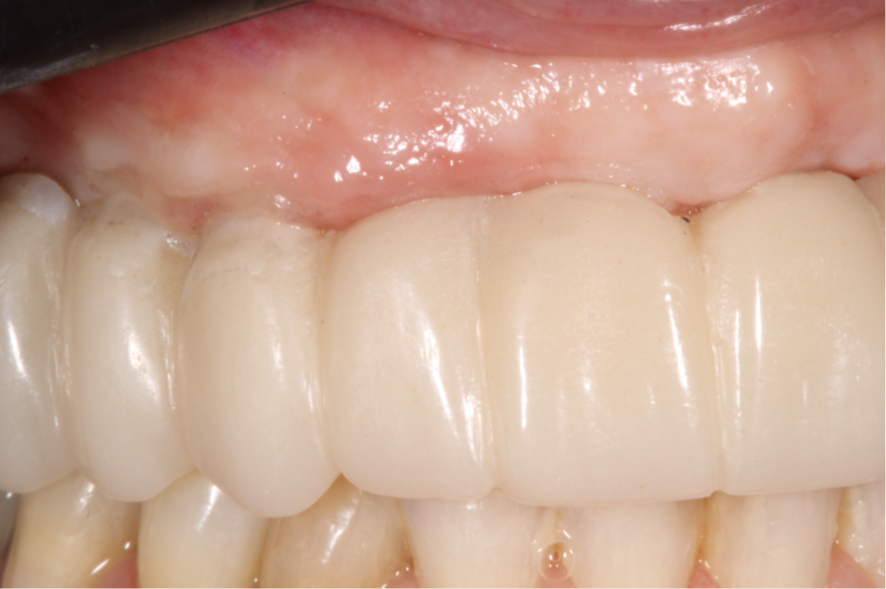

Após o período de osseointegração, verificamos que o implante na região do elemento 12 não apresentava tecido mole para o correto perfil de emergência.

Optamos então por substituir o componente protético do elemento 12, de Mini Cônico 4,8 mm de diâmetro e 2,5 mm de cinta gengival, para Micro Cônico 3,5 mm de diâmetro e 1,5 mm de cinta gengival.